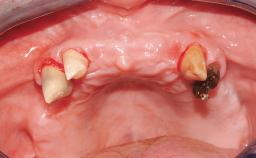

Transition from an “irrational to treat” Maxillary Dentition to a Full-Arch Segmented FDP by Early Loading of Eight Implants Placed Using the Staged Approach

The staged approach permits the transition from an “irrational to treat”dentition to a full arch implant supported restoration without any need to use a removable provisional prosthesis or to apply the immediate-placement and immediate-loading techniques.  A failing dentition is the usual indication for a staged treatment. On the other hand, the dentition should still contain many residual teeth, but with few or none of them being suitable for use as definitive abutments for a full-arch fixed restoration.This situation is usually the result of advanced periodontal disease or of the failure of an extensive fixed prosthesis.

Case Type Edentulous Maxilla

# of Teeth All

Periodontal Status History of periodontitis or genetic predisposition